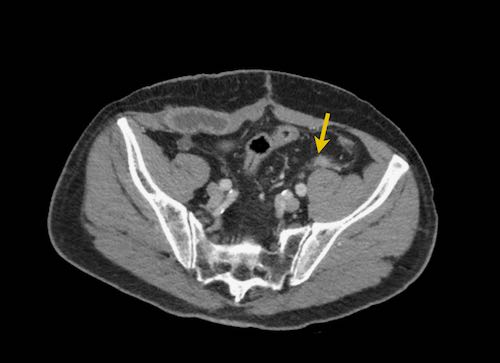

Hình ảnh

Hình ảnh CT của một bệnh nhân ung thư phúc mạc.

Một lượng nhỏ dịch cổ trướng hiện diện ở góc phần tư trước bên phải.

Các đường dày dạng nốt vuông góc với thành ruột được ghi nhận.

Hình ảnh này đại diện cho tổn thương xâm lấn mạc treo ruột lan rộng (mũi tên).